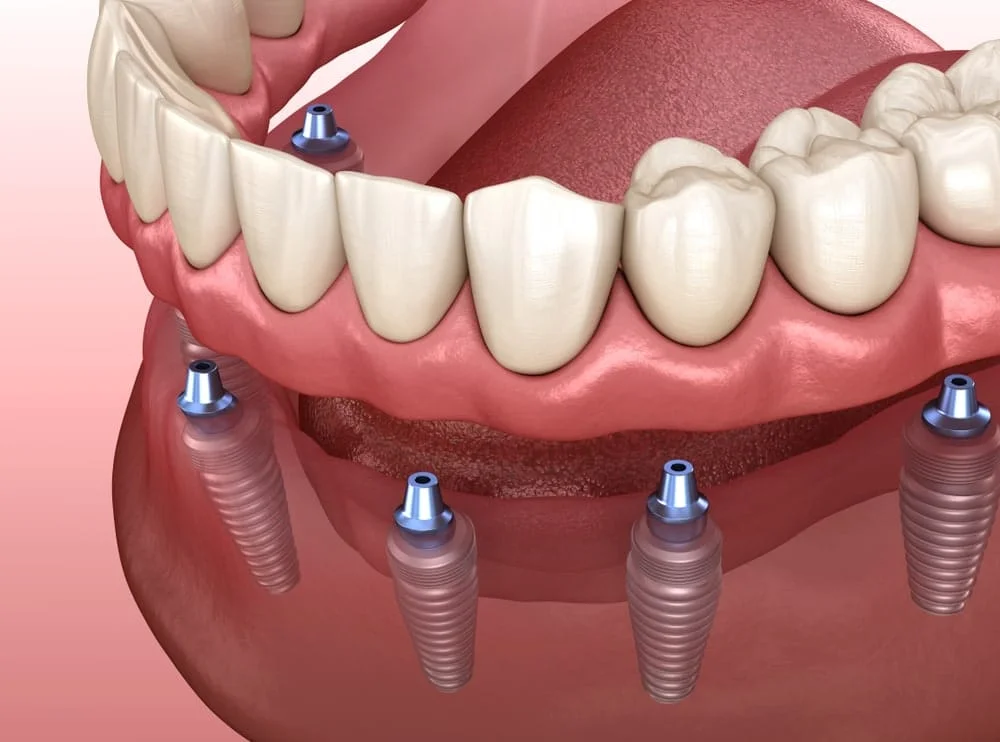

IMPLANTOLOGIE

L'implantologie permet de remplacer les dents manquantes avec des implants durables et esthétiques. Dr. Anas Moumen utilise des technologies avancées pour restaurer votre sourire de manière naturelle et fonctionnelle.